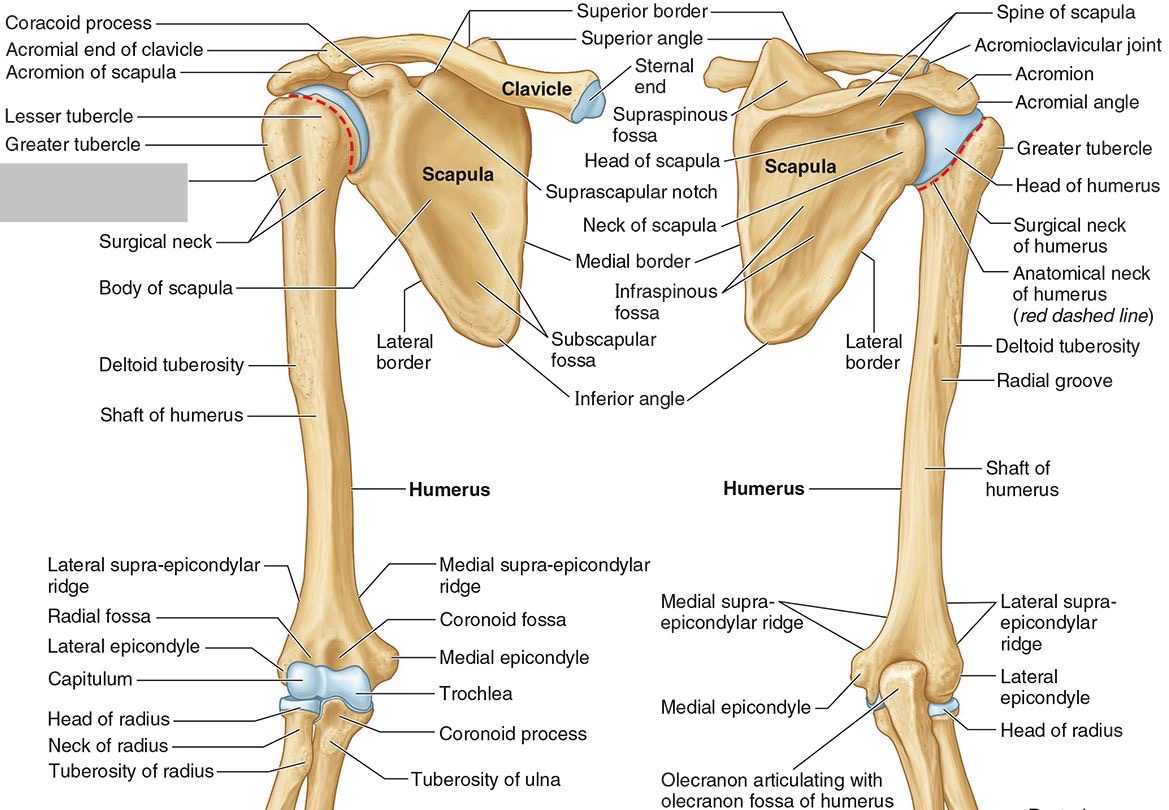

What part of the humerus is this?

The head of the humerus articulates with the scapula at the glenohumeral joint.

What part of the humerus is this?

The anatomic neck is an indentation distal to the head and provides an attachment for the fibrous joint capsule of the glenohumeral joint.

What part of the humerus is this?

The greater tubercle lies lateral and distal to the anatomic neck.

What part of the humerus is this?

The lesser tubercle lies on the anterior/medial side of the humerus, just distal the anatomic neck.

What part of the humerus is this?

The intertubercular (bicipital) groove lies between the greater and lesser tubercles.

What part of the humerus is this?

The surgical neck is a narrow area distal to the tubercles. It is a common site for proximal humerus fractures.

What part of the humerus is this?

The humeral shaft features the deltoid tuberosity laterally for the distal insertion of the deltoid muscle.

What part of the humerus is this?

The radial groove is an oblique depression that contains the radial nerve and deep brachial artery.

Which parts of the humerus is this?

The medial and lateral epicondyles are distal prominences to which many forearm tendons attach, near the elbow joint.

Which parts of the humerus is this?

The medial and lateral supracondylar ridges extend superiorly from the medial and lateral epicondyles.

Which parts of the humerus is this?

The trochlea and the capitulum (the condyles) are the most distal surfaces of the humerus, where it articulates with the forearm bones at the elbow joint

What part of the humerus is this?

The olecranon fossa is a posterior depression above the trochlea that receives that olecranon process of the ulna

What part of the humerus is this?

The coronoid fossa is an anterior depression above the trochlea that receives that coronoid process of the ulna.